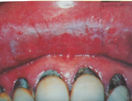

广东从化的张鑫(化名),曾经患上唇炎,总感觉到嘴唇周围胀紧硬,干裂红肿溃烂流脓出血脱皮。经过检查,结果使唇轻度角化不全、皮突延长、表皮可见较多空泡样细胞,真皮浅层血管明显扩张,血管周围稀疏的炎细胞浸润,为慢性唇炎症状。

张鑫治疗前